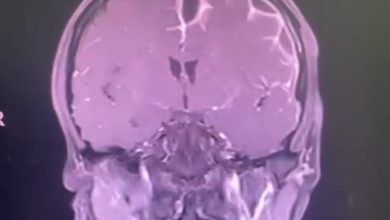

عملية جراحية في الرأس تعيد الحركة لمصابة بالشلل

نجح فريق طبي من قسم جراحة المخ والاعصاب في مستشفى الملك فهدبالهفوف من إعادة الحركة لمريضة تعاني من شلل تام…